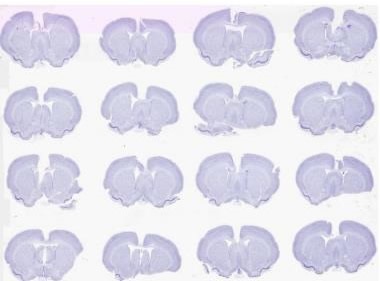

Brightfield scan of 16 Nissil stained rodent brains on a 2” x 3” slide at 0.5 μm

Figure 2. Brightfield scan of 16 Nissil stained rodent brains on a 2” x 3” slide at 0.5 μm. Image credit: Huron Digital Pathology.